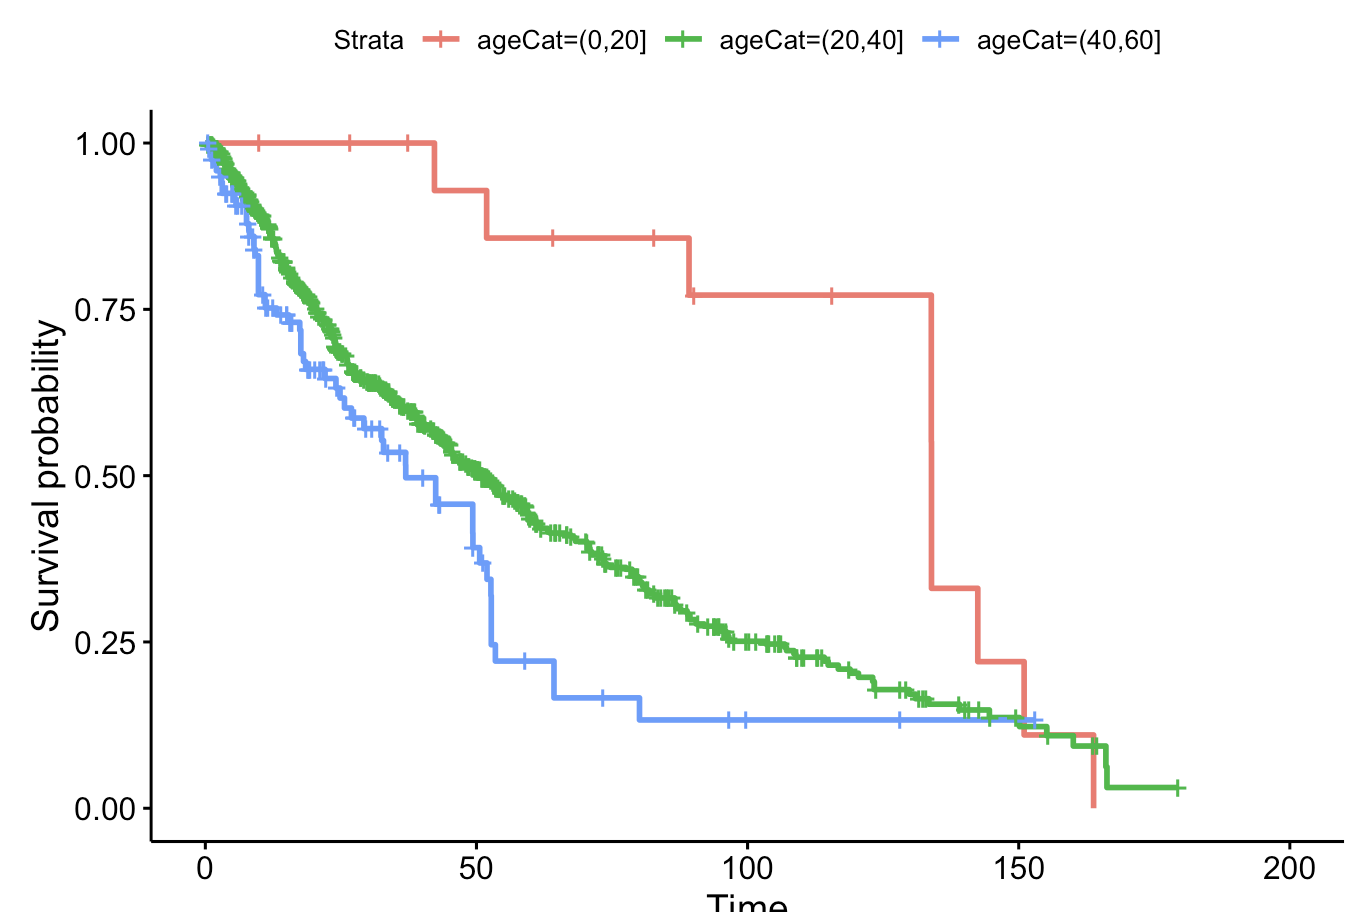

Analysis of Breast Cancer Treatments

Will Madairy ’21 (Charlotte, North Carolina),

Applied mathematics & statistics

-

How do differing breast cancer treatments compare in effectiveness? When considering which treatment is best, we would expect for more invasive procedures to lead to greater survival outcomes, but is this truly the case? Using data from the Netherland Cancer Institute, we were able to analyze survival outcomes across different treatments. In this analysis we compare outcomes for patients who underwent chemotherapy, hormonal, and amputation treatments and determine if any of the treatments leads to longer survival time compared to others.